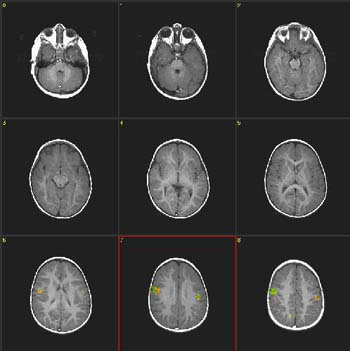

fMRI Studies (Functional Magnetic Resonance Imaging)

What is fMRI?

Functional magnetic resonance imaging (fMRI) is a development of MRI techniques that allows visualization of brain functions related to specific tasks. The study does not require any substance to be administered since it is based on the indigenous brain vascular response, requiring only cooperation for periods ranging from 15 to 60 minutes.

To date, several tasks have been utilized for mapping the brain cortex. Simple tasks include stimuli based on presentation of light, colors, tones, chords, music, syllables, movement of fingers and basic sensory perceptions. More complex and refined experiments have been implemented to map subtle cognitive functions. Currently, there is a vast armamentarium for mapping memory, attention, inhibition, face recognition, sensory discrimination, fear, etc.

However, most fMRI work has been directed in mapping language. Language mapping has been performed in children and adults. Reading, listening to meaningful text, generating words, making semantic decisions, are the most frequent paradigms described in the abundant current literature on fMRI. The technique has received ample acceptance among neuroscientists interested in epilepsy for the potential it has to become a tool to replace the Wada test.

Functional MRI is based on small signal changes that result from the following cascade of events. A task elicits activation in one or several brain areas. These areas increase their metabolic demands, suffer vasodilatation, and alter their levels of deoxyhemoglobin and oxyhemoglobin. Since deoxyhemoglobin is a paramagnetic molecule, it influences the phase of local proton-spins, altering the source signal that is converted into images. Therefore, the image is a representation of local changes of levels of deoxyhemoglobin, related to the brain region performing a task.

Although fMRI is almost risk-free, it cannot be performed in patients with claustrophobia, metal implants, wires and pace-makers. Patients with vagal nerve stimulators, or dental braces, may be included. However, some degradation of the images is expected.

Research and studies conducted by:

Dr. Nolan Altman and Dr. Byron Bernal of the Radiology Department

Clinical Cases Language Mapping Auditory Mapping 3D fMRI